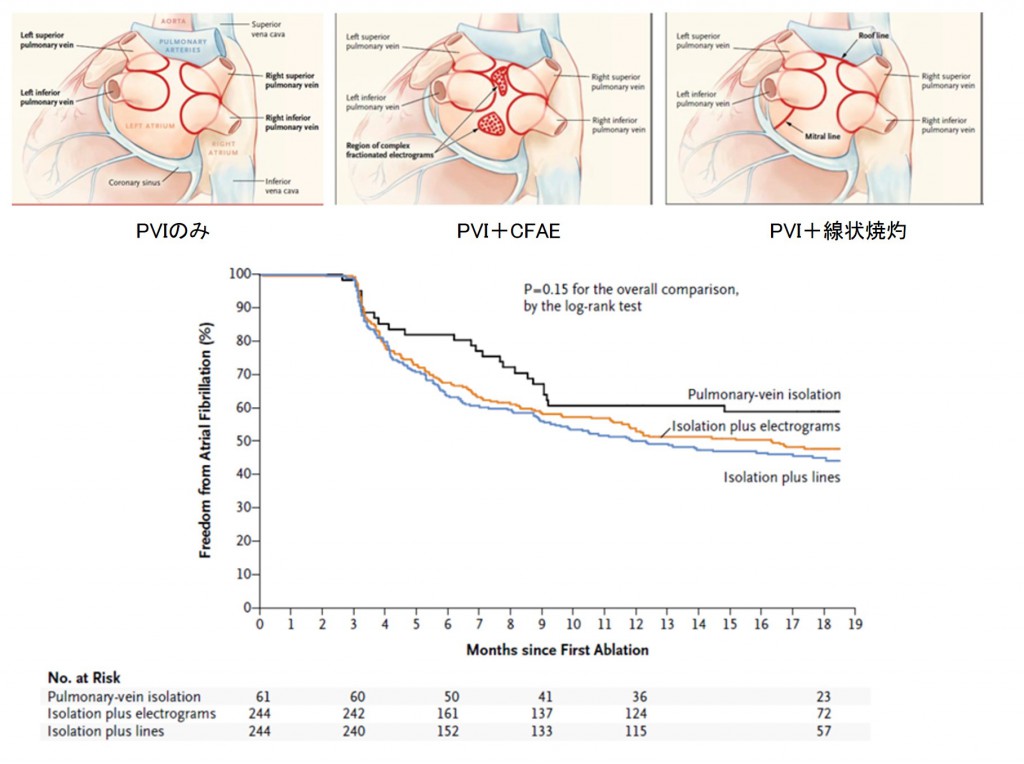

(1) Approaches to Catheter Ablation for Persistent Atrial Fibrillation

N Engl J Med. 2015 May 7;372(19):1812-22.

P (population): 持続性AF患者 589例

I (intervention): PVIにCFAEアブレーション追加(263例)もしくはPVIに線状焼灼追加(259例)

C (control): PVI単独(67例)

O (outcome): PVIにCFAEアブレーションもしくは線状焼灼を追加しても、持続性AFの再発を減らすことはできなかった。

ひとつ目はSTAR-AF Ⅱ Trialです。その後のアブレーション方針に非常に大きな影響を与えました。この試験結果はアブレーターにとってある意味ショッキングなものでした。良かれと思って頑張って行ってきた追加アブレーションの効果が否定されてしまったのです。しかも、合併症のテーブルを見ますと(表)、左房食道瘻に伴う死亡例がCFAE追加例で生じています!アブレーションに関連する数ある合併症の中で最も致死的なものが左房食道瘻です。これは左房後面に接している食道が焼灼の熱によって障害されて生じる合併症です。頻度は非常に希ですが、一度生じると致死的です。1例でも生じてほしくない重大合併症がNEJMに掲載されるような大規模試験に参加する施設で生じている事実は重く受け止めなければならないでしょう。もちろんこの試験の結果だけで全てのCFAEアブレーションや線状焼灼の意義が否定された訳ではありませんが、追加アブレーションにはリスクが伴うことを術者はしっかり胸に刻んでおかねばなりません。

図7:アブレーション方法(上段)および成績(下段)

表:手技に伴う合併症。